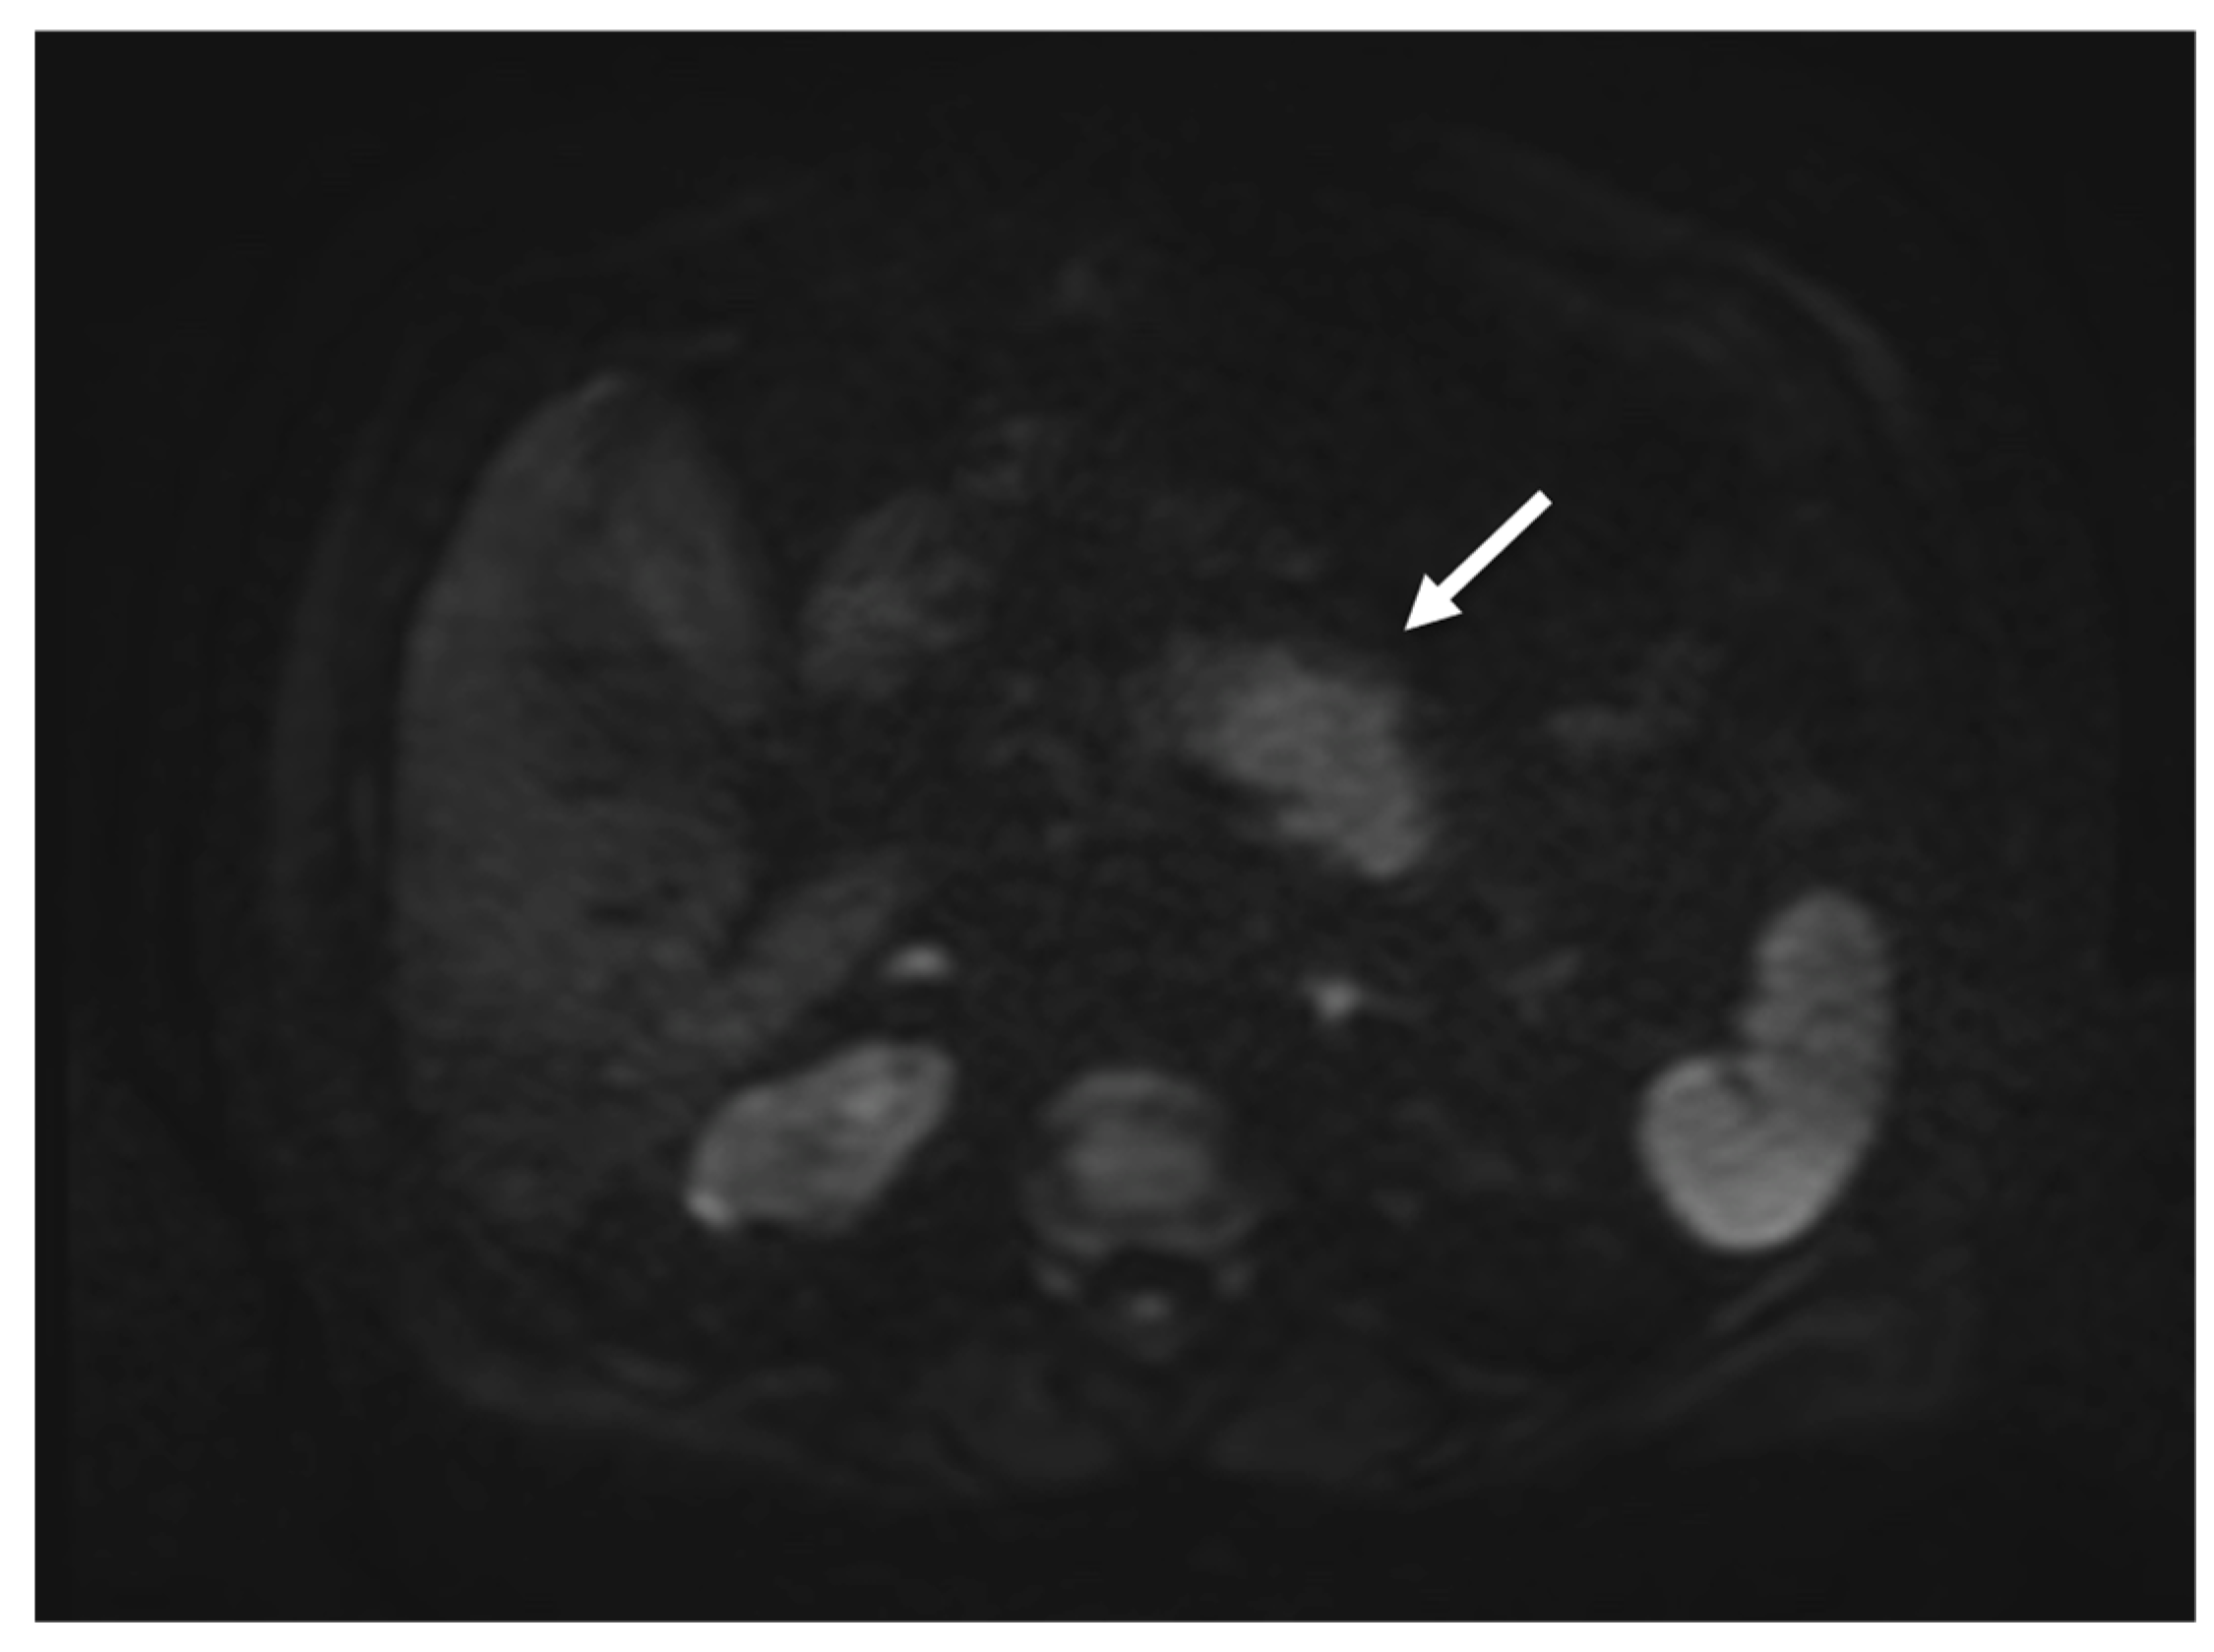

2. Case Report